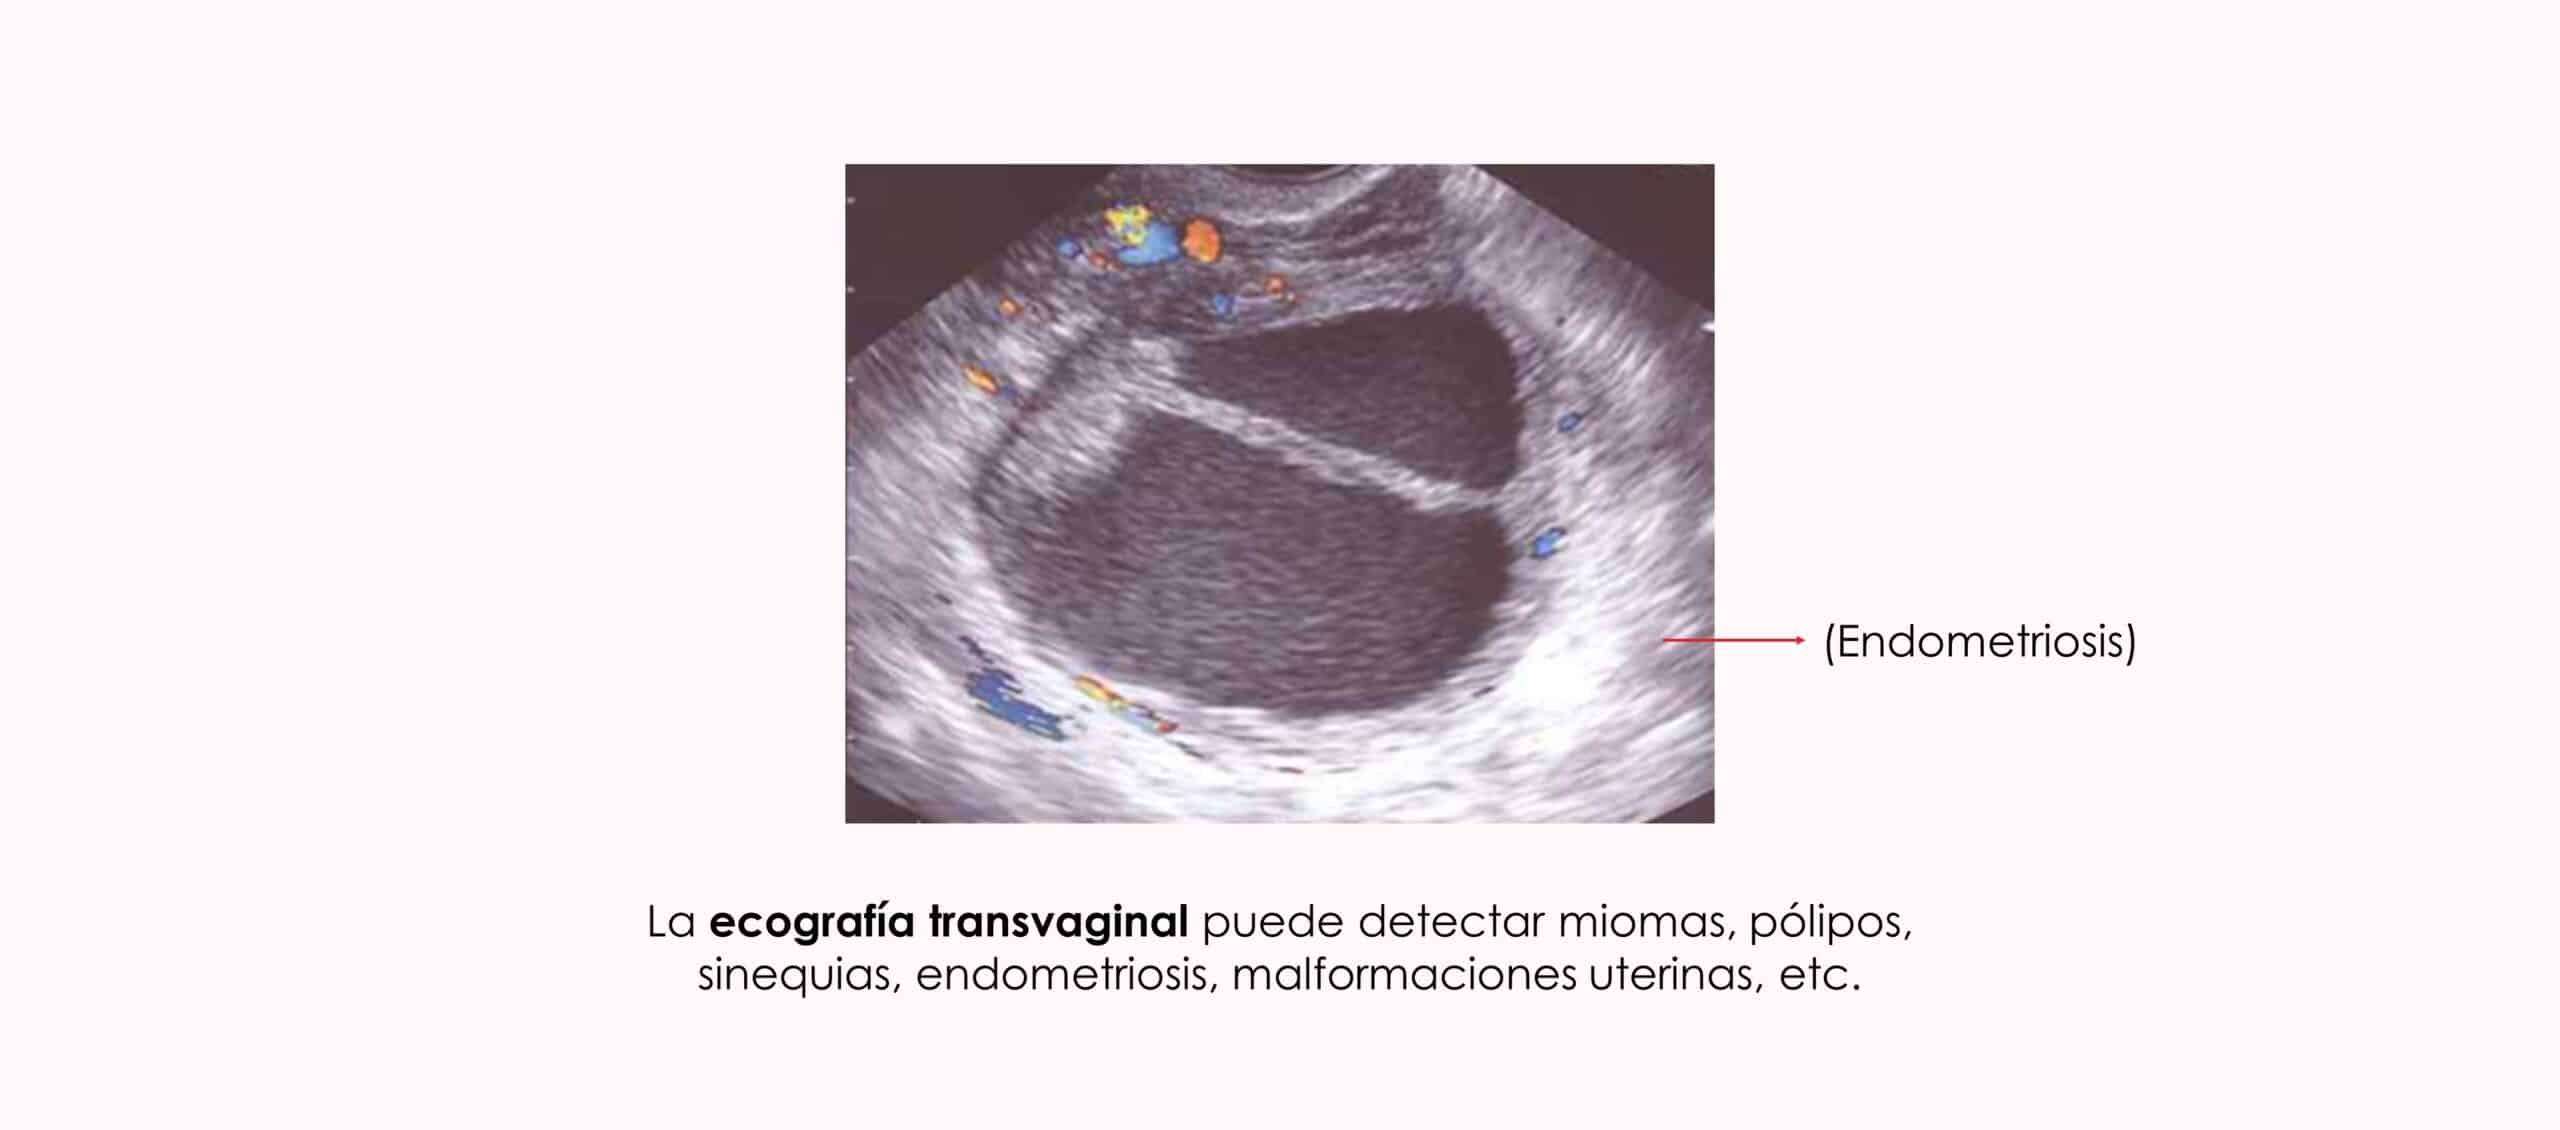

Endometriosis

La endometriosis constituye una causa muy importante de infertilidad. La endometriosis se asocia con adenomiosis y ambas pueden afectar negativamente al pronóstico reproductivo.